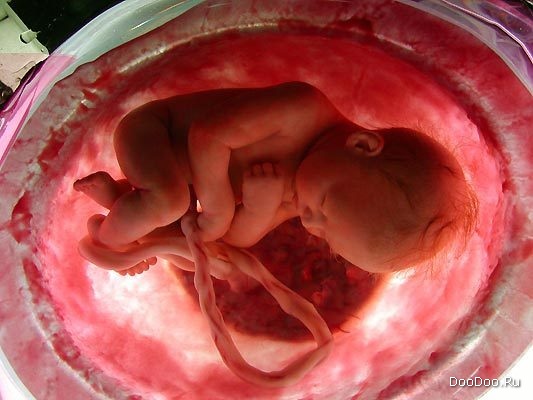

Шестой месяц. Почти полностью сформирован зародыш.

Последние стадии беременности. Его пять чувств уже активны.